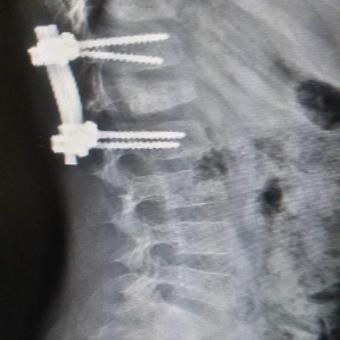

l1l2腰椎横突骨折图

l1l2腰椎横突骨折图,腰椎234横突骨折图